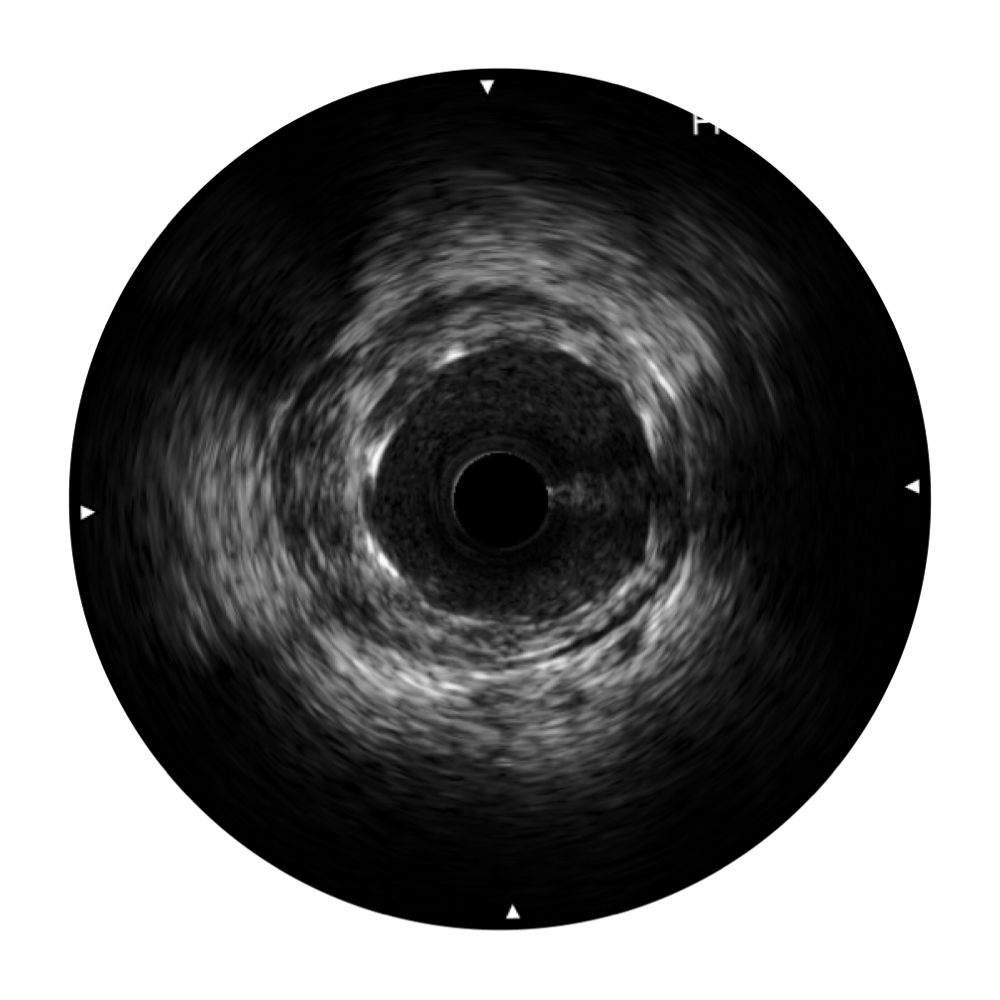

传统IVUS图像

对比传统IVUS导管成像,百老汇电子游戏官网宽频IVUS图像的近场支架梁显影更细腻,远场中膜外血管仍清晰可辨,兼顾远中近,兼顾分辨力与穿透深度